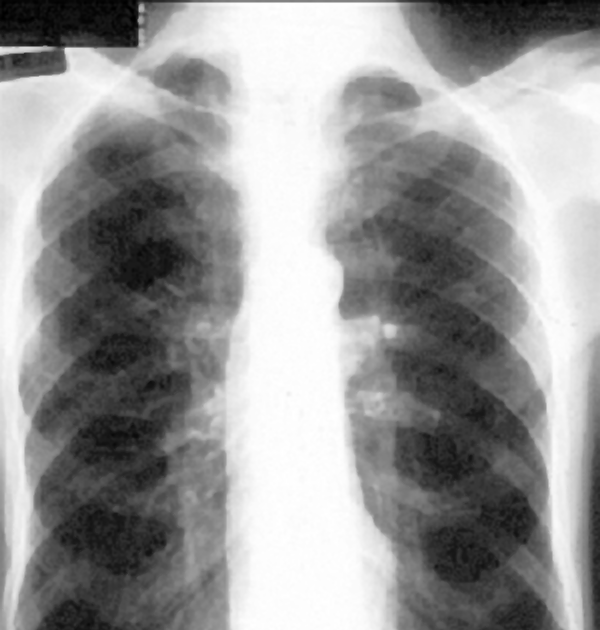

Phimaimedicine 941. Chest Xrays of chronic obstructive pulmonary Image Of Chest X Ray With Copd It uses electromagnetic radiation to create pictures of the lungs,. This image shows no abnormality at the left lung base. Tap on/off image to show/hide findings. Comparison of the two images makes it. This means that the lung tissue is expanded and the lungs appear larger than. Copd lungs often appear hyperinflated compared to healthy lungs. Image Of Chest X Ray With Copd.

COPD Findings on PosteriorAnterior and Lateral Chest Xray Findings Image Of Chest X Ray With Copd Tap on/off image to show/hide findings. This image shows no abnormality at the left lung base. It uses electromagnetic radiation to create pictures of the lungs,. Copd lungs often appear hyperinflated compared to healthy lungs. This means that the lung tissue is expanded and the lungs appear larger than. Comparison of the two images makes it. Image Of Chest X Ray With Copd.

Image Of Chest X Ray With Copd . This means that the lung tissue is expanded and the lungs appear larger than. Comparison of the two images makes it. This image shows no abnormality at the left lung base. It uses electromagnetic radiation to create pictures of the lungs,. Tap on/off image to show/hide findings. Copd lungs often appear hyperinflated compared to healthy lungs.